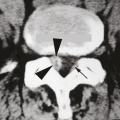

Spécificités du kyste synovial articulaire postérieur

Un kyste synovial développé aux ­dépens d’une articulation interapophysaire postérieure peut provenir de l’arrière et comprimer l’émergence d’une racine nerveuse (fig. 3). Il constitue une cause relativement fréquente de lomboradiculalgie du sujet d’âge mur. Ce kyste se développe à partir d’une arthropathie postérieure dégénérative, habituellement érosive, et est associé dans deux tiers des cas à un spondylolisthésis dégénératif.9 Une injection de corticoïdes dans l’articulation postérieure à l’origine du kyste permet de faire céder durablement la radiculalgie dans un tiers des cas. En revanche, si la radiculalgie persiste ou récidive sous bref délai (< 6 mois), de nouvelles injections sont, en règle générale, inefficaces. Il faut donc recourir à l’exérèse chirurgicale du kyste, parfois associée à une stabilisation, s’il existe des signes d’instabilité vertébrale.9